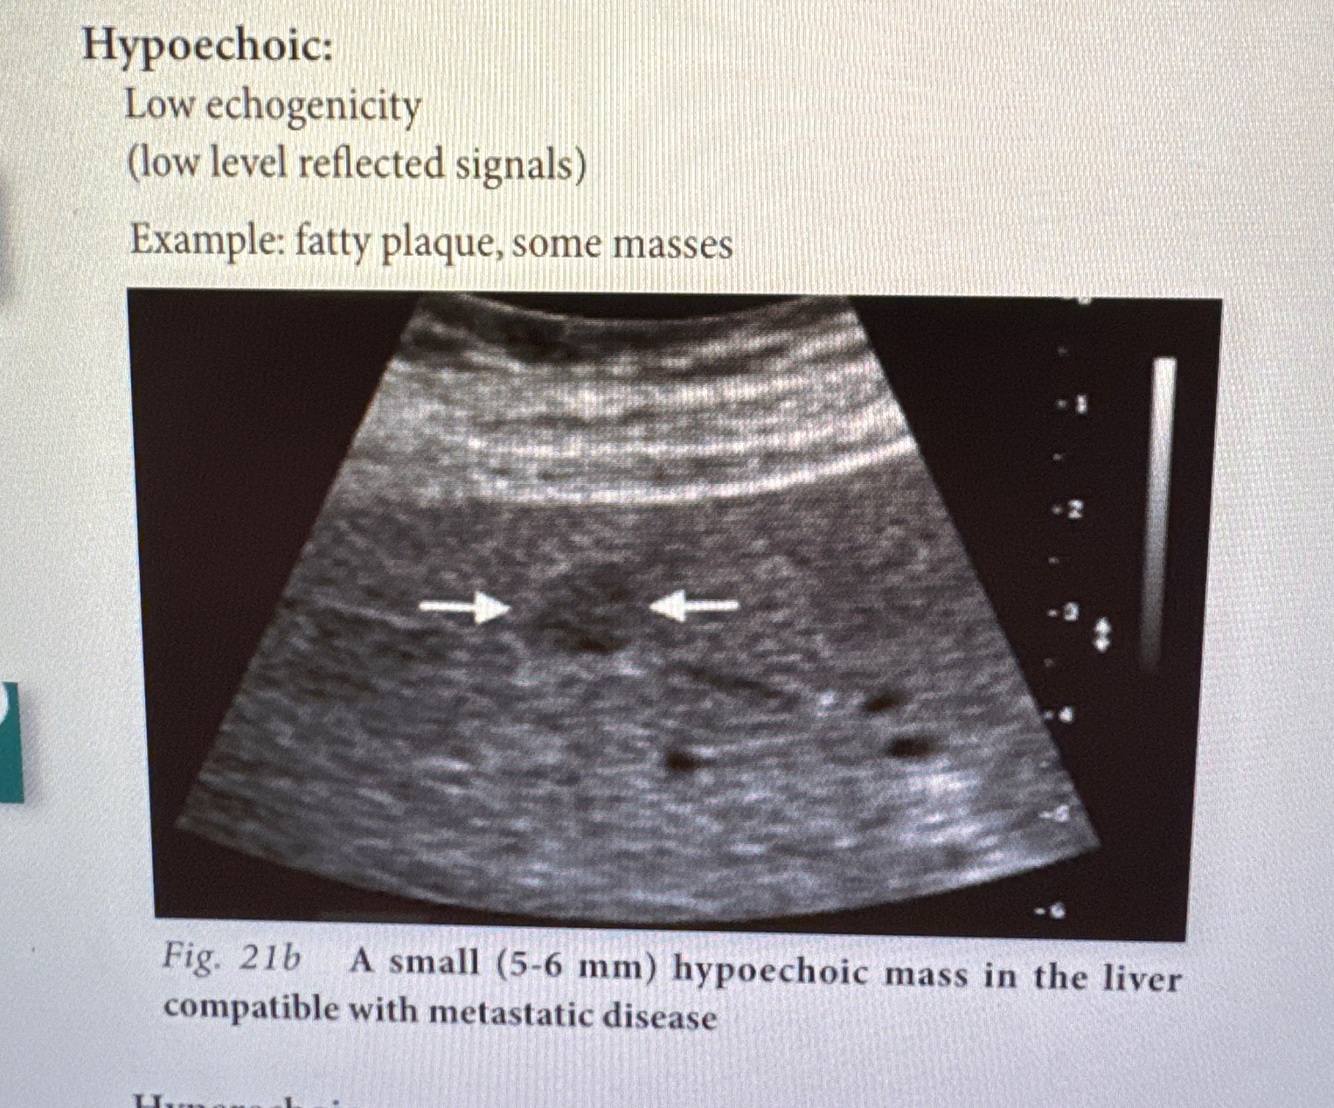

What is hypoechoic

• low echogenecity (low level reflected signals)

• fatty plaque, some masses